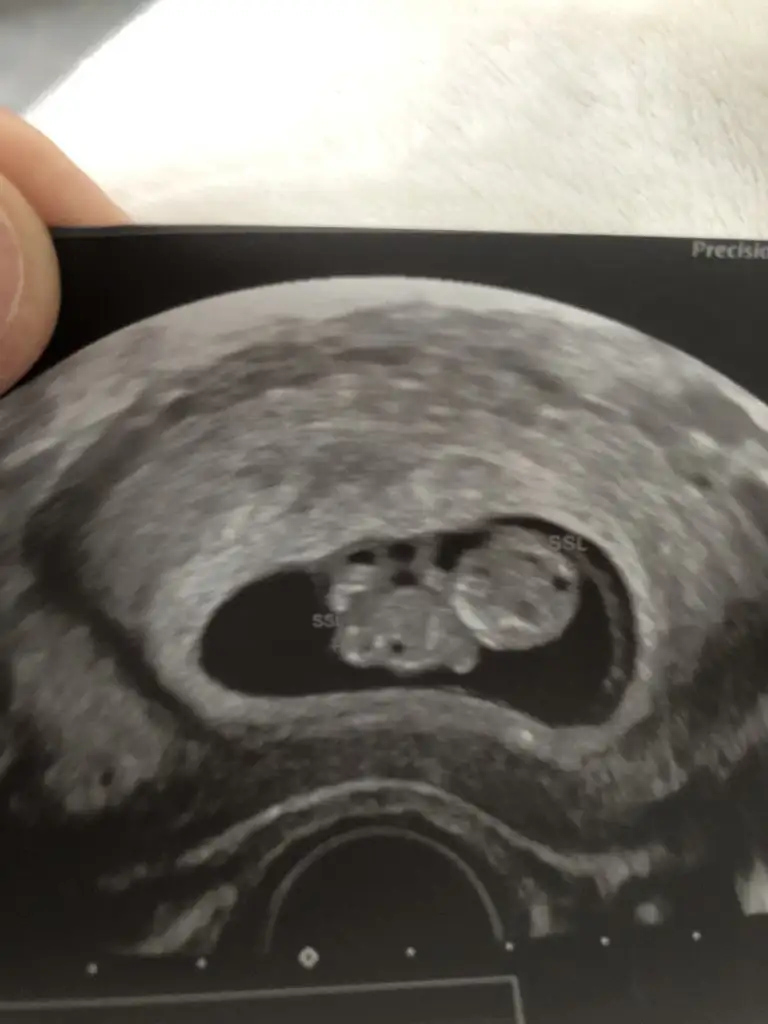

Ikra meyra Ikra meyra Merhaba cnm nasılsın :) benim iki bebeğiminde cinsiyet tahminini doğru yorumlamıştın oğlum 7 aylık oldu bile :) bu bebişide yorumlar mısın lütfen :)

• 49777C8C-2DEE-4861-BECC-D529F8F185D1.webp

49777C8C-2DEE-4861-BECC-D529F8F185D1.webp

35,8 KB · Görüntüleme: 96

10+3 nub için küçük şimdilik kız yönünde ama en iyi 11 12 13 haftalar paylasin 🤗 maşallah minnoslara 🧿🧿